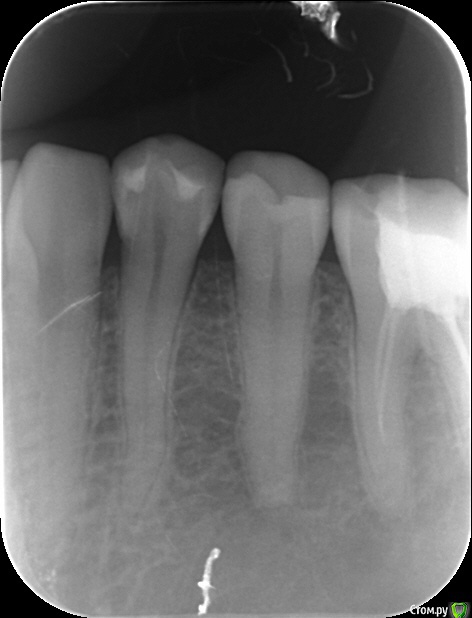

В июле обратилась в стоматологию, в которой был в наличии Бифлюорид. И там на цифровом рентгене (снимок прилагаю) диагностировали еще один пришеечный кариес. Пролечили. Боль с жевательной поверхности исчезла. Но до боковой поверхности дотронуться невозможно. Болеть стало уже на стоматологическом кресле при шлифовке при отхождении действия укола. Потерпела, сколько могла. Пришла в августе опять. Опять наложили более толстый слой. Опять лучше, но боль есть.

Прилагаю два снимка. От 18 июля, это когда обнаружили повторно кариес. От 9 августа - после всех пломбировок. На июльском снимке хирург (ходила отдельно со снимком на консультацию) диагностирует расширение периодонтальной щели. Другие врачи не видят!!! На августовском снимке щель уже не видна, она что могла самоизлечиться?

Есть ли фиброзный периодонтит? Удалять нерв? Чем опасно расширение периодонтальной щели? Нерв рекомендовал удалить по снимку хирург, но он сам терапевтическое лечение не оказывает, а рекомендуемый им врач утверждает, что нет показаний для удаления нерва, периодонтальную щель не видит. СПАСИБО!